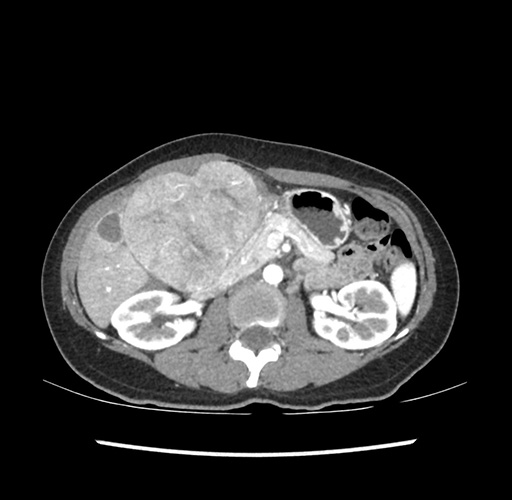

Imaging Analysis

Look through the patient's CT scan to identify any areas of concern for the necessary procedure.

Based on your CT findings, which issue(s) would give reason for "planned slowing down moment(s)" in this case?

Considering a standard left lateral sectionectomy procedure, what step(s) of the operation would you do differently in this case ?